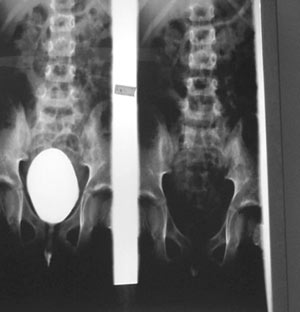

Εικόνα

1. Κυστεογραφία αρνητική για ΚΟΠ.

αριστερά χωρίς διάταση του συστοίχου ουρητήρα, ανιούσα κυστεοουρηθρογραφία στην

οποία δεν διαπιστώθηκε ΚΟΠ (εικόνα 1), DTPA στο οποίο διακρίνεται καθαρά η αποφρακτική

καμπύλη του αριστερού νεφρού, ειδικά μετά την έγχυση φουροσεμίδης (εικόνα 2).